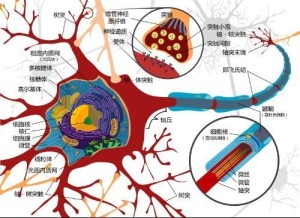

功能:接受刺激和传递信息 突触 神经纤维 胞体 树突 : 较短,一